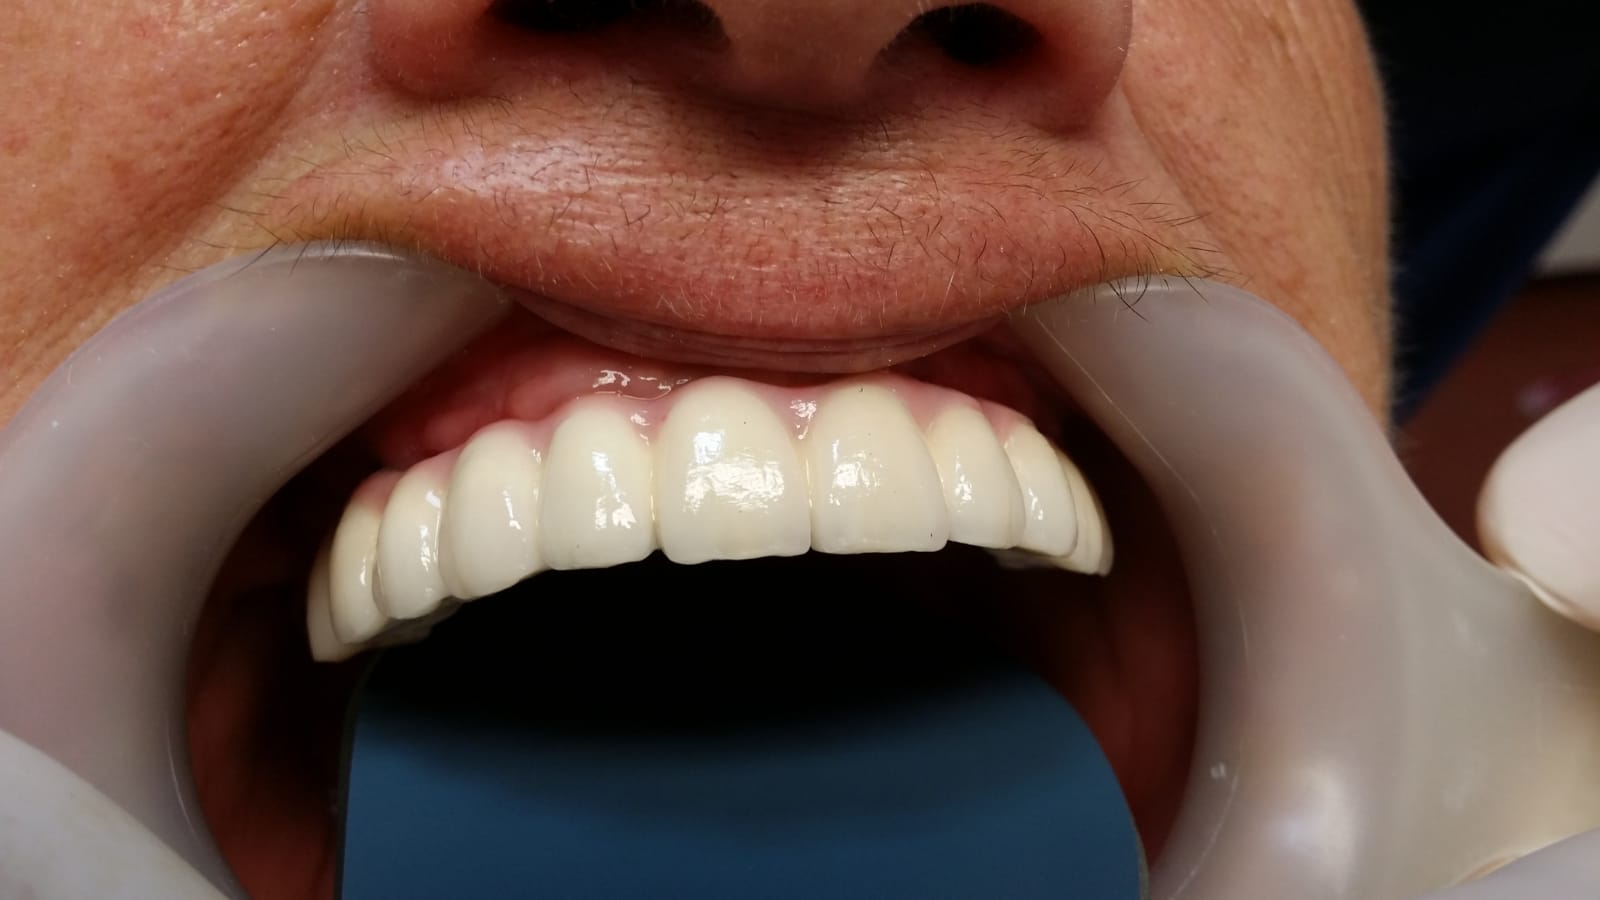

Fast and fixed definitiv

Punți metaloceramice total fizionomice pe implanturi

Punti totale pe implanturi